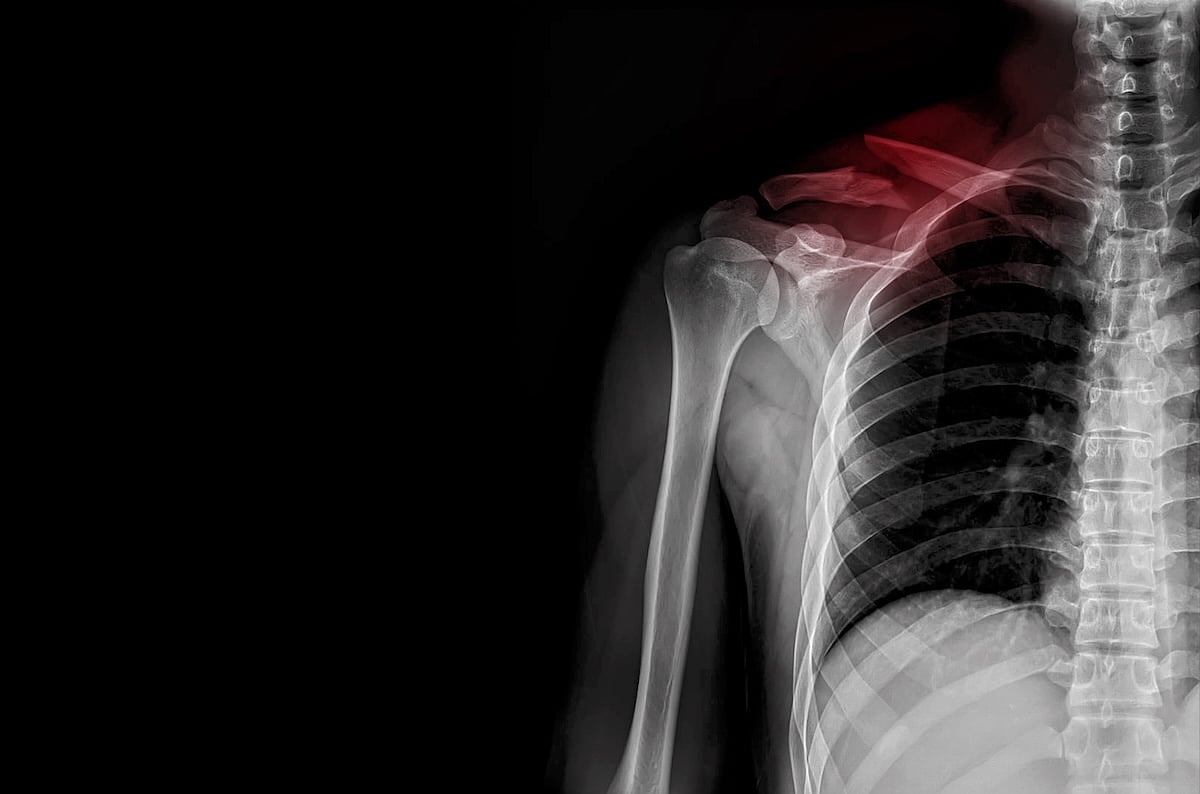

Broken Collarbone Hospitalizations Increase Among Children

More kids are being hospitalized for broken collarbones, a new study has found.

In fact, the hospitalization rate for broken collarbones more than doubled among children between 2014 and 2021, researchers reported.

The hospitalization rate for broken collarbones rose to a high of 2.6% in 2021 from a low of 0.8% in 2014, researchers report.